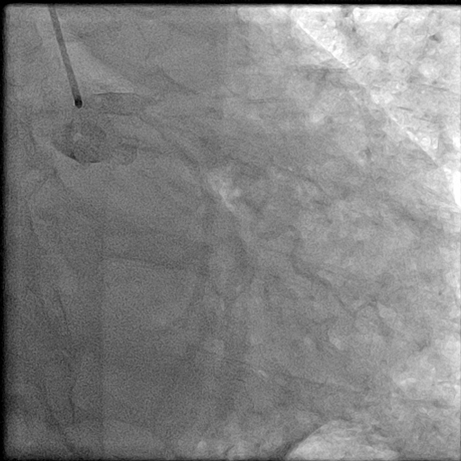

【临床病例】心肌梗死、心力衰竭患者心室率控制不佳怎么办?--新型If通道阻滞剂的应用

文章来自:中山二院心脏病MDT 叶伟斌 张坤